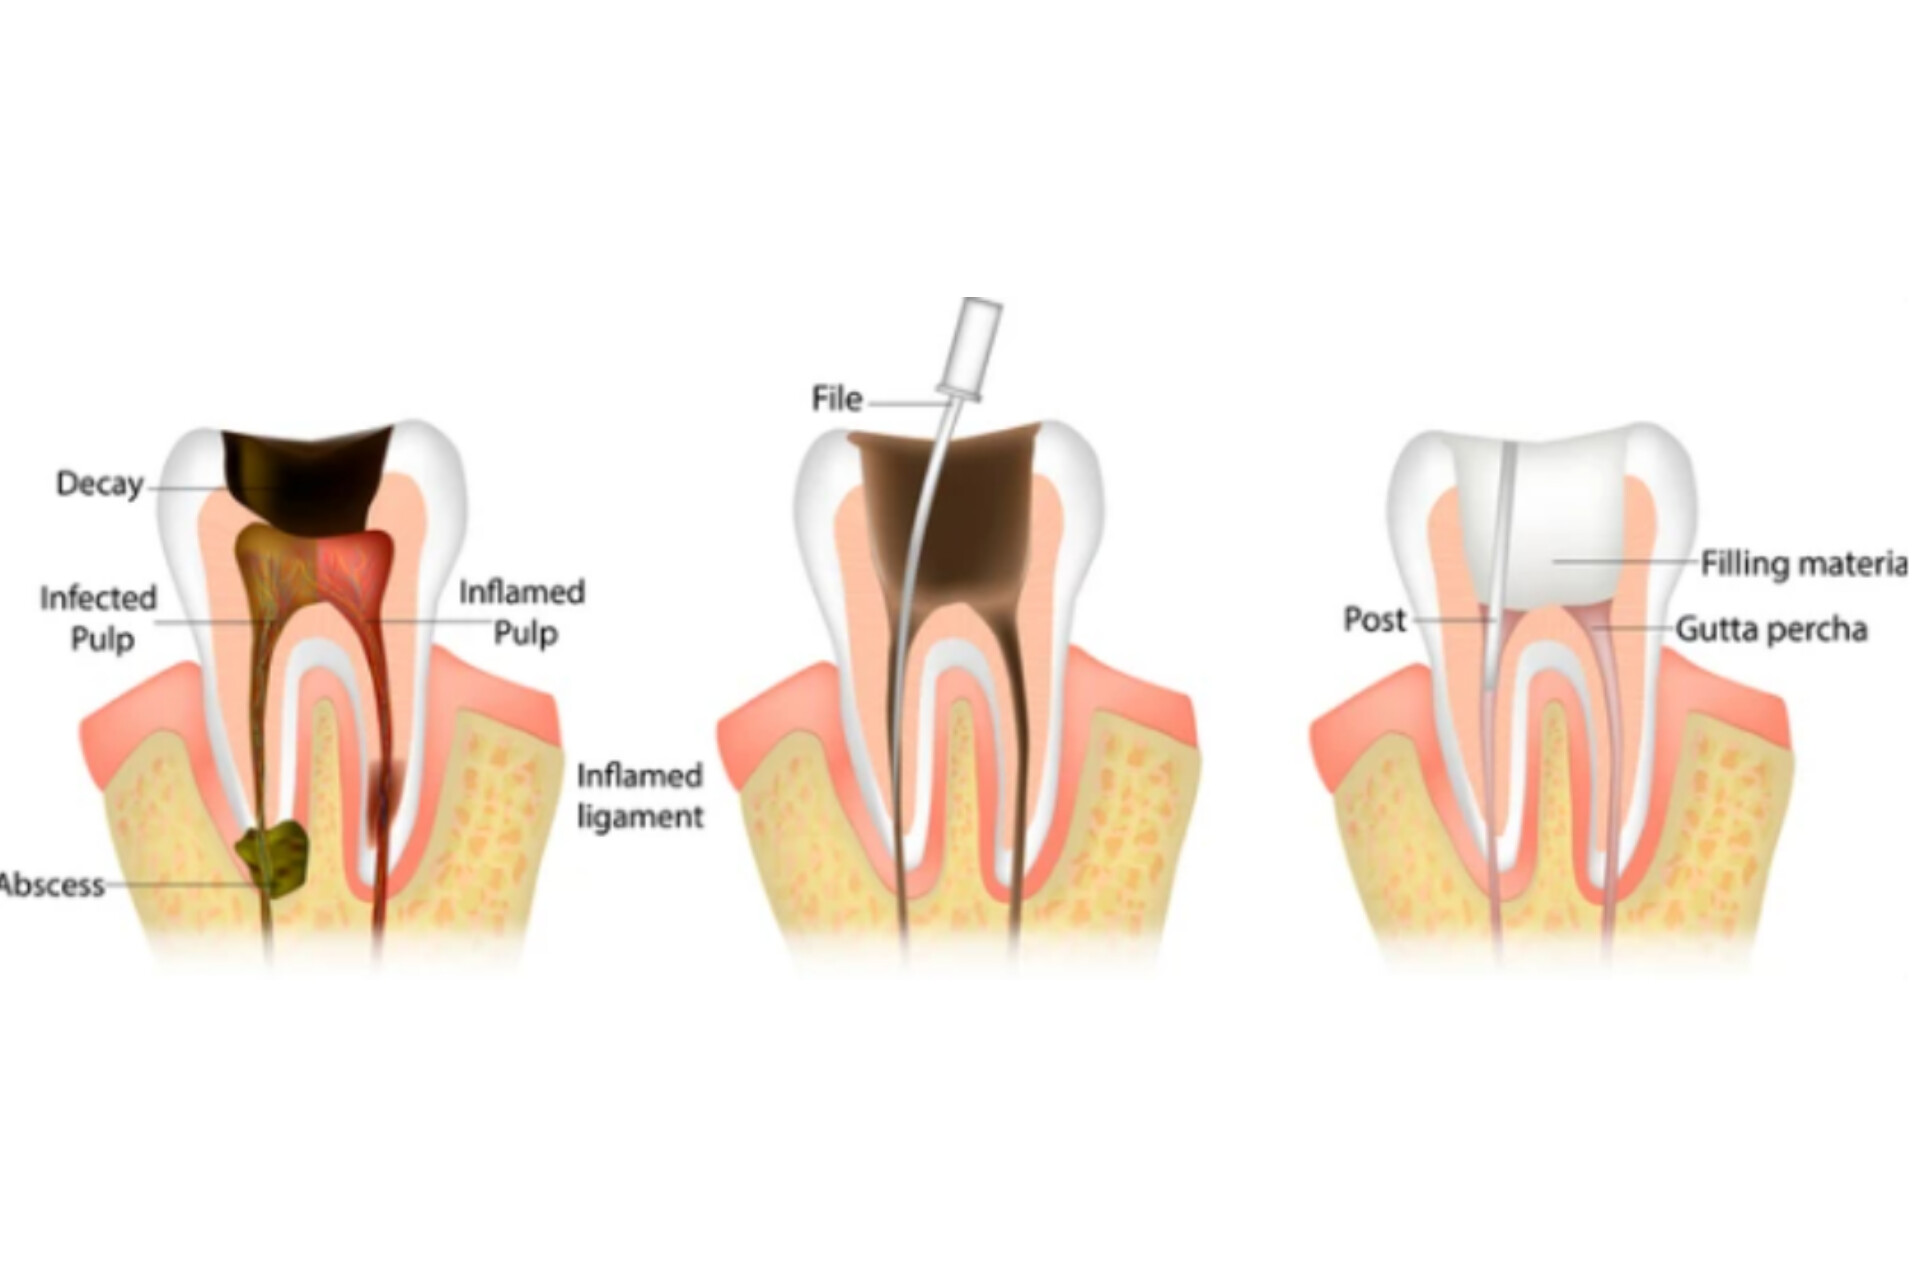

Root canal Treatment

Root canal treatment is an often straightforward procedure to relieve dental pain and save your teeth. Patients typically need a root canal when there is inflammation or infection in the roots of a tooth. During root canal treatment, an endodontist who specializes in such treatment carefully removes the pulp inside the tooth, cleans, disinfects and shapes the root canals, and places a filling to seal the space.